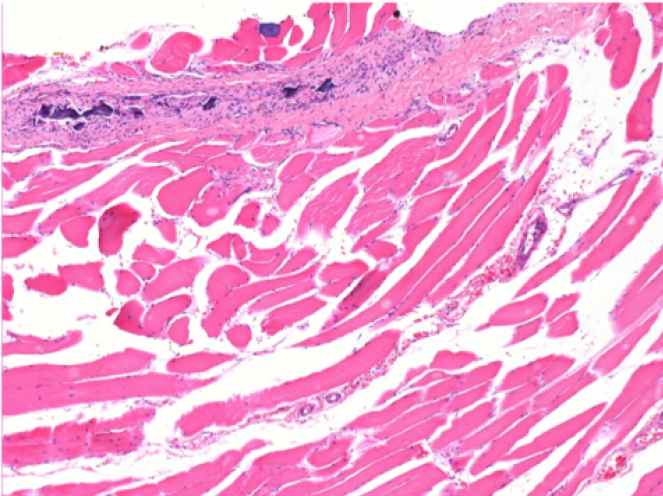

1 month after Endopeel Injection

1 month after Endopeel Injection 0.1ml in the right pretibial muscle.

What is seen in black on the pictures is not a necrosis like could imagine some scientifics !

In fact, 4 conclusions have to be taken in consideration

- an artefact of coloration

- an absence of necrosis

- an apoptosis

- a bioregenerative process

L : Control-100xD30

R:100xD30

R :400xD30